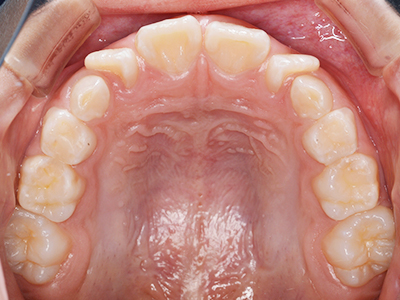

歯並びの相談に来られるお子様は、口呼吸をしているケースが多く、これが歯並びに大きな影響を与えています。

↓ - 上あごが狭くなる

ないき歯科クリニックでは、上あごの成長不足を補い、鼻呼吸を獲得しつつ歯列を整え、将来のお口をより健康な状態にすることをゴールに定める矯正治療をおこなっています。